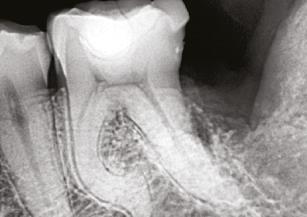

Figures 1A-1B: Two periapical radiographs of tooth No. 24 taken at different angles. Resorptive defect changes position relative to root canal, which according to buccal object rule, means defect is separate from canal and, hence, external to canal

While external root resorption comes in many forms, such as transient surface resorption, pressure resorption, external inflammatory root resorption, invasive cervical root resorption, and replacement resorption (ankylosis), internal root resorption is uniquely different. The differential diagnosis is made by taking multiple radiographs at different angles.9,10 Utilizing the buccal object rule, a lesion of internal origin will remain close to the canal regardless of the angle, while a lesion of external origin will move away from the canal depending on the angle of the radiograph (Figures 1A and 1B).

Additionally, with IRR, the outline of the root canal is usually distorted and appears contiguous with the resorptive defect, while with external resorption, the root canal outline appears normal and can usually be seen running through the radiolucent resorptive defect, as there remains a thin layer of dentin separating the canal from the resorptive area9-10 (Figures 2A-2D).

The radiographic appearance of IRR is a fairly uniform radiolucent enlargement of the root canal. There would only be alveolar bone loss adjacent to the resorption if the resorption perforates into the PDL. The best and most accurate tool we have for diagnosing IRR and determining the path of the perforating

lesion is cone beam computed tomography (CBCT). It is best to use a limited field of view (FOV), as opposed to the larger FOV used with other disciplines in dentistry. A smaller FOV increases image resolution, while at the same time providing a lower effective radiation dose to the patient. It is worth noting that in Case 2, one cannot visualize the resorptive defect from just looking at the periapical radiograph. It has been shown in countless studies that CBCT gives a more accurate diagnosis and better visualization of periapical pathology.11-13